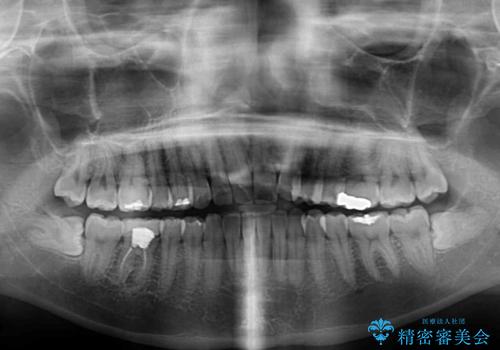

- 矯正治療の後戻りが気になるとのことで来院された患者様です。

上顎の後戻りをインビザライン・ライトで治療することとしました。

上顎のみの治療を希望されたため、咬み合わせをしっかりと改善することはできませんでしたが、審美面が大きく改善され、日常生活の機能面でも不具合を感じることはなく、大変満足していただきました。